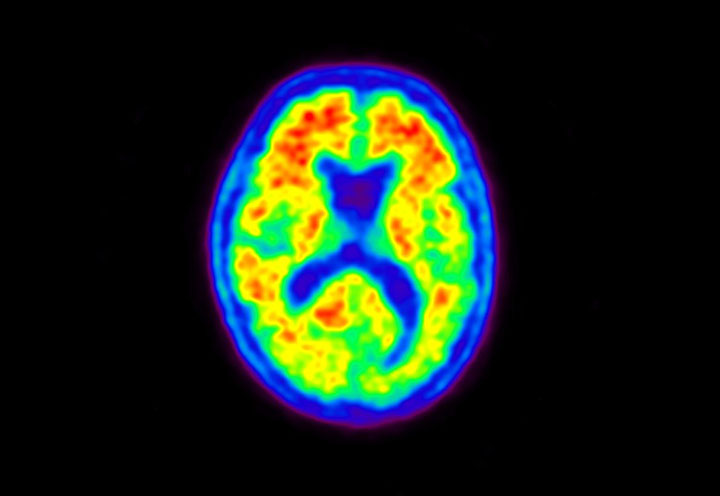

Head / Case5 : Amyloid

Courtesy : Kindai University Hospital

- Imaging protocol

- Injected dose: 4.27 MBq/kg, 18F-Flutemetamol

- Uptake time: 99 minutes

- Scan time: 20 minutes